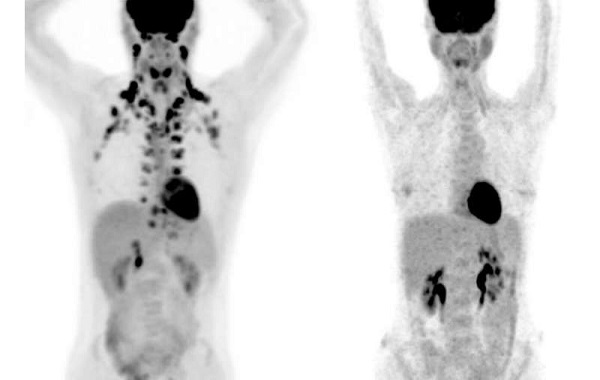

Large-scale studies of brown fat, however, have been practically impossible because this tissue shows up only on PET scans, a special type of medical imaging. “These scans are expensive, but more importantly, they use radiation,” says Tobias Becher, the study’s first author and formerly a Clinical Scholar in Cohen’s lab. “We don’t want to subject many healthy people to that.”

A physician-scientist, Becher came up with an alternative. Right across the street from his lab, many thousands of people visit Memorial Sloan Kettering Cancer Center each year to undergo PET scans for cancer evaluation. Becher knew that when radiologists detect brown fat on these scans, they routinely make note of it to make sure it is not mistaken for a tumor. “We realized this could be a valuable resource to get us started with looking at brown fat at a population scale,” Becher says.

In collaboration with Heiko Schoder and Andreas Wibmer at Memorial Sloan Kettering, the researchers reviewed 130,000 PET scans from more than 52,000 patients, and found the presence of brown fat in nearly 10 percent of individuals. (Cohen notes that this figure is likely an underestimate because the patients had been instructed to avoid cold exposure, exercise, and caffeine, all of which are thought to increase brown fat activity).